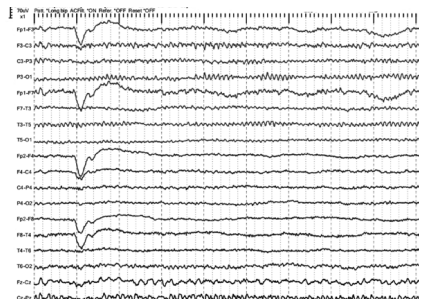

Assinale a alternativa abaixo que indica um possível diagnóstico para o traçado a seguir (sensibilidade = 7 uV/mm).

Ritmo de falha óssea, ou tipo brecha, em hemisfério cerebral esquerdo.

Hematoma extradural sobre a convexidade cerebral direita.

AVC de artéria cerebral média esquerda, fase crônica.

Desorganização difusa da atividade elétrica cerebral.

Variante alfa lento em hemisfério cerebral esquerdo.